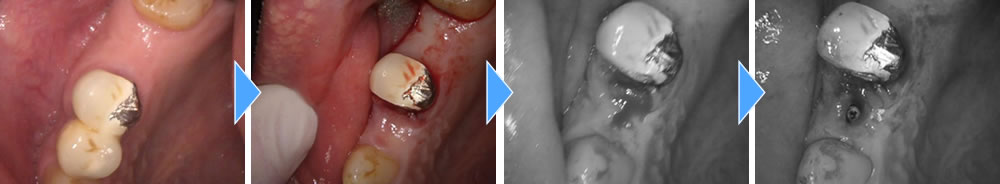

元々歯のない前歯には、最小限の切開(8ミリ程度)にてインプラントの埋入と共に仮の歯を装着し、見た目も即日で回復していきました。

手術後3ヵ月間は治癒期間を設け、しっかりと骨とオステオインテグレーションしている事を確認し、上部の歯を作成していきました。

結果、しっかりと噛む事ができ、審美的にも回復する事ができました。